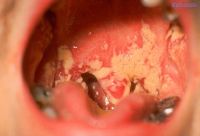

Какие–то поражают только слизистые оболочки и живут во рту, в виде кандидозов и стоматитов или во влагалище в виде кандидозов и вагинитов.

3. Часто приходят люди и показывают на ладонях, на тыльных сторонах, что-то непонятное, как – будто покарябано – обожжено. Всё, что на руках, под мышками, в паховых складках – это все грибы. Если откуда–то выделяется что-то белое, творожистое – то это тоже грибы. Неважно, изо рта ли, влагалища, или бронхов, миндалин.

4. Всё, что на языке белое, творожистое, крупинчатое – это все грибы. Вечером спать легли – язык был нормальный, утром встали – обложен белым налетом. Белый налет - это и есть грибок. Лимфатическая система всю ночь собирает этот белый налет на ворсиночках языка, как на ковриках у двери, откладывает, потому что дальше он идет на выброс. Слущивается с языка и вместе с питанием выплевывается, либо отхаркивается.